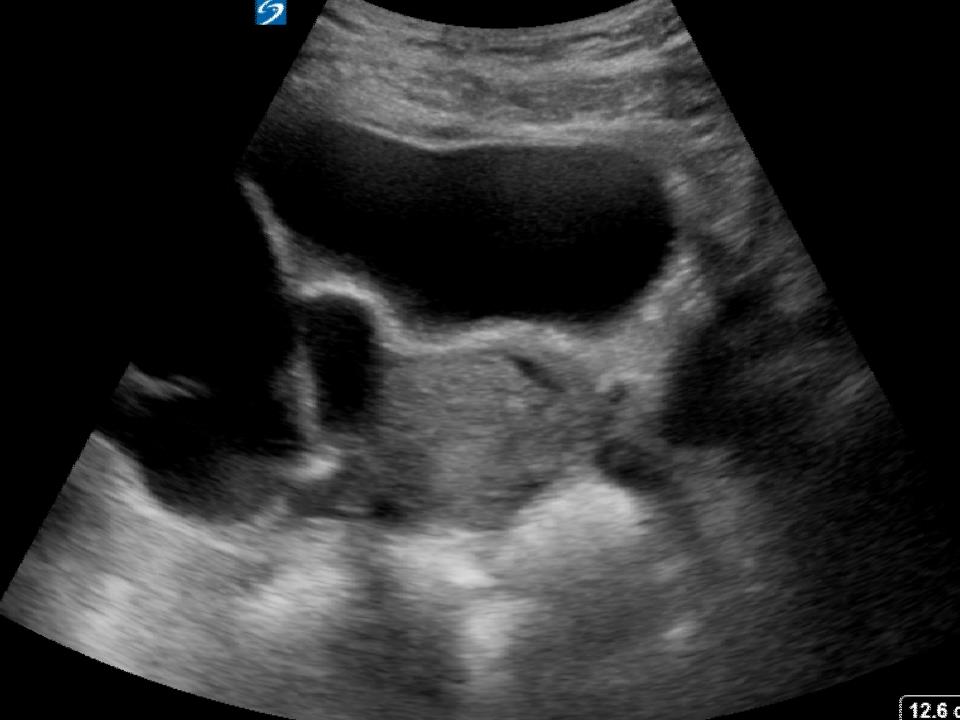

Free fluid in pouch of Douglas in ultrasound scan(POD free fluid) YouTube What Are The Causes Of Fluid In The Pouch Of Douglas The presence of free fluid in the pouch of douglas can be attributed to both physiological and pathological causes. Free fluid in the cul de sac, a small pouch located between the back of the uterus and the rectum, can indicate various health. The fluids that collect regularly during the menstrual cycle are the. What are the physiological causes which.. What Are The Causes Of Fluid In The Pouch Of Douglas.